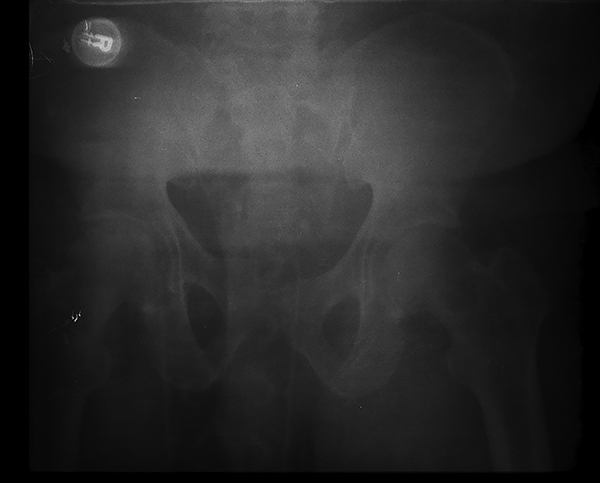

Figure 2. Patient with APC2 Fracture After Placement of a Pelvic Binder |

Placement of the pelvic binder with approximation and stabilization of the anterior and posterior elements, resulting in decreased pelvic volume. Source: Uzcategui M, Menaker J. Blunt pelvic trauma. Trauma Reports 2014;15:6. |